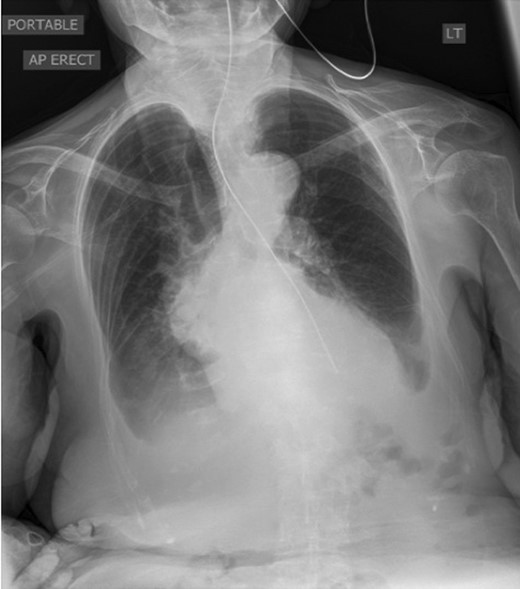

A 95-year-old Caucasian woman presented with worsening dysphagia, epigastric pain, retching without vomiting and hiccups over 5 months. Oesophagogastroduodenoscopy (OGD) was unsuccessful due to failed intubation. Fibreoptic nasoendoscopy revealed pooling of saliva in the piriform fossa and a diagnosis of pharyngeal pouch was initially made. Barium swallow was abandoned due to aspiration by the patient (Fig. 1).

Sequence of barium swallow examinations revealing upper oesophageal tightening and aspiration.